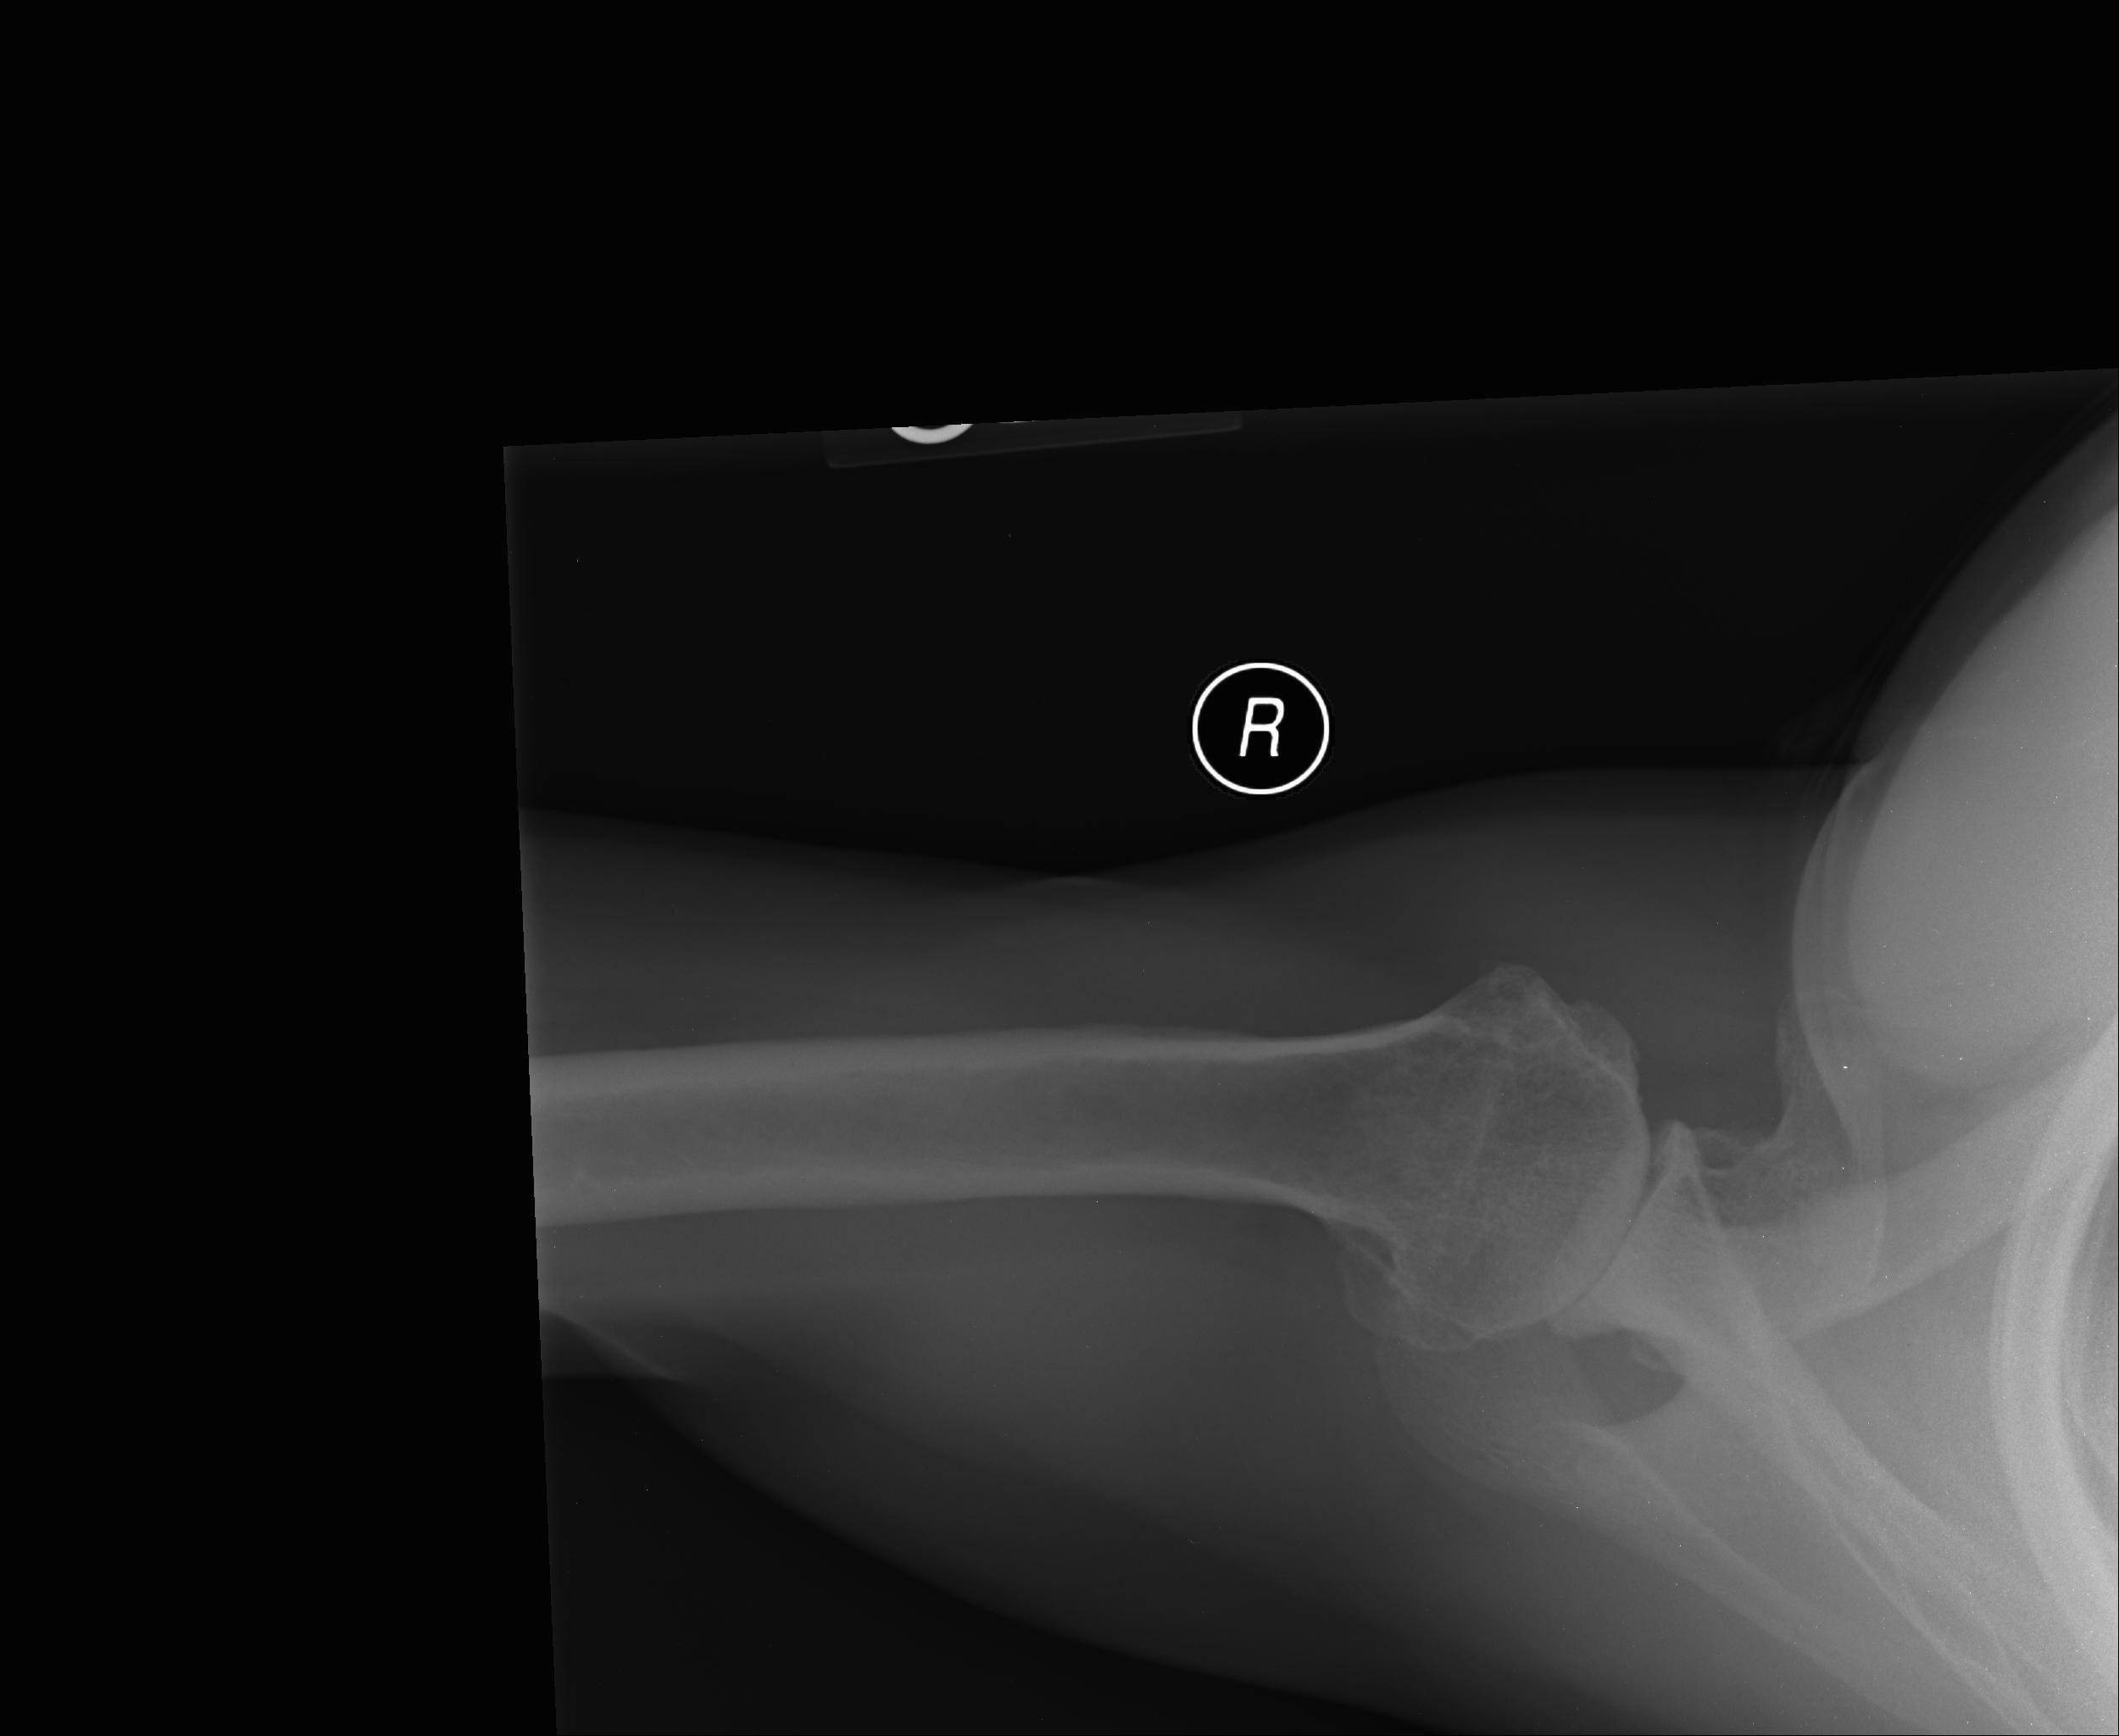

Shoulder X Ray Axillary View . Mri is best for evaluating soft tissue structures and evaluating bone contusions or trabelcular microfractures. On the ap radiograph the humeral head is usually in internal rotation and higher than normal. The axial shoulder view is a supplementary projection to the lateral scapula view for obtaining orthogonal images to the ap. The posterior position of the humeral head can be shown on the scapular “y” view or axillary view. Lateral/scapula y view (named due to the “y”. This view provides excellent visualization of the humeral head and neck, though it is typically painful for the patient since it requires shoulder abduction. The anterior humeral head can impact against the posterior glenoid rim, which. The axillary view is useful for detecting anterior or posterior shoulder dislocations that are not evident in the ap view. Often, the humeral head is subluxed, rather than completely dislocated.